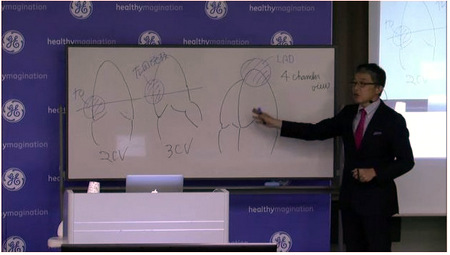

■10分でわかる「動画で確認できるECHO講座」

熟練医師の実技やコメントの動画で、GE製品の使用シーンを具体的に紹介。使い方のコツを動画で見て確認することができる。

第1回講座:LOGIQ iMを活用した腹部超音波スクリーニング走査法(26断面)をのぞいてみよう!

第2回講座:LOGIQ E9を使った小川先生の腹部超音波スクリーニングをのぞいてみよう!

第3回講座:LOGIQ E9 を使って胆嚢を高周波プローブで見てみよう。